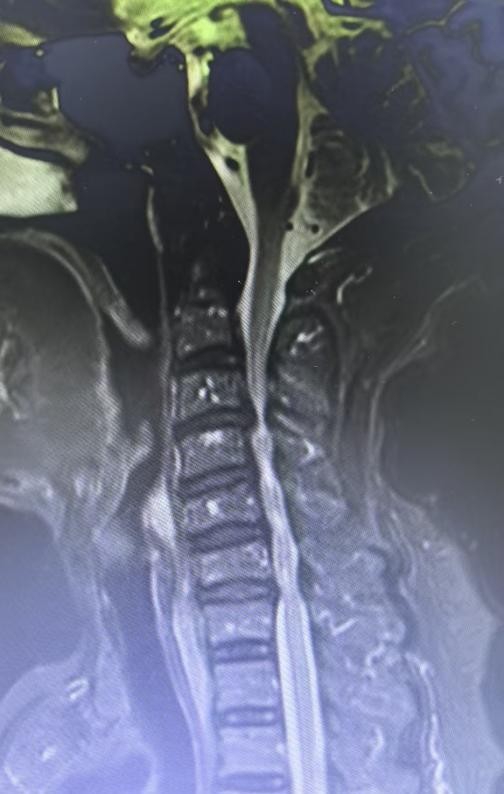

门诊医生迅速展开查体,并安排颈椎 MRI 检查,结果显示颈椎退行性变,C3/4 椎间盘突出伴后方脊髓信号改变,C4/5 椎间盘突出伴后方脊髓信号改变。基于这些检查结果,患者被诊断为 “脊髓型颈椎病伴颈部脊髓损伤” 等复杂病情,随即以 “颈部脊髓损伤” 收入院准备接受手术治疗。

11 月 1 日,手术如期进行。脊柱科手术团队在麻醉医师配合下,麻醉患者并摆位。林科院长借导航系统定位,于 C4 椎体平面颈前右侧作切口,逐层解剖显露,C 型臂机辅助确定椎间隙,处理椎体与椎间盘减压,植入钛网、钢板并固定,C 臂确认位置,止血、核查无误后放引流管,逐层关切口完成手术。